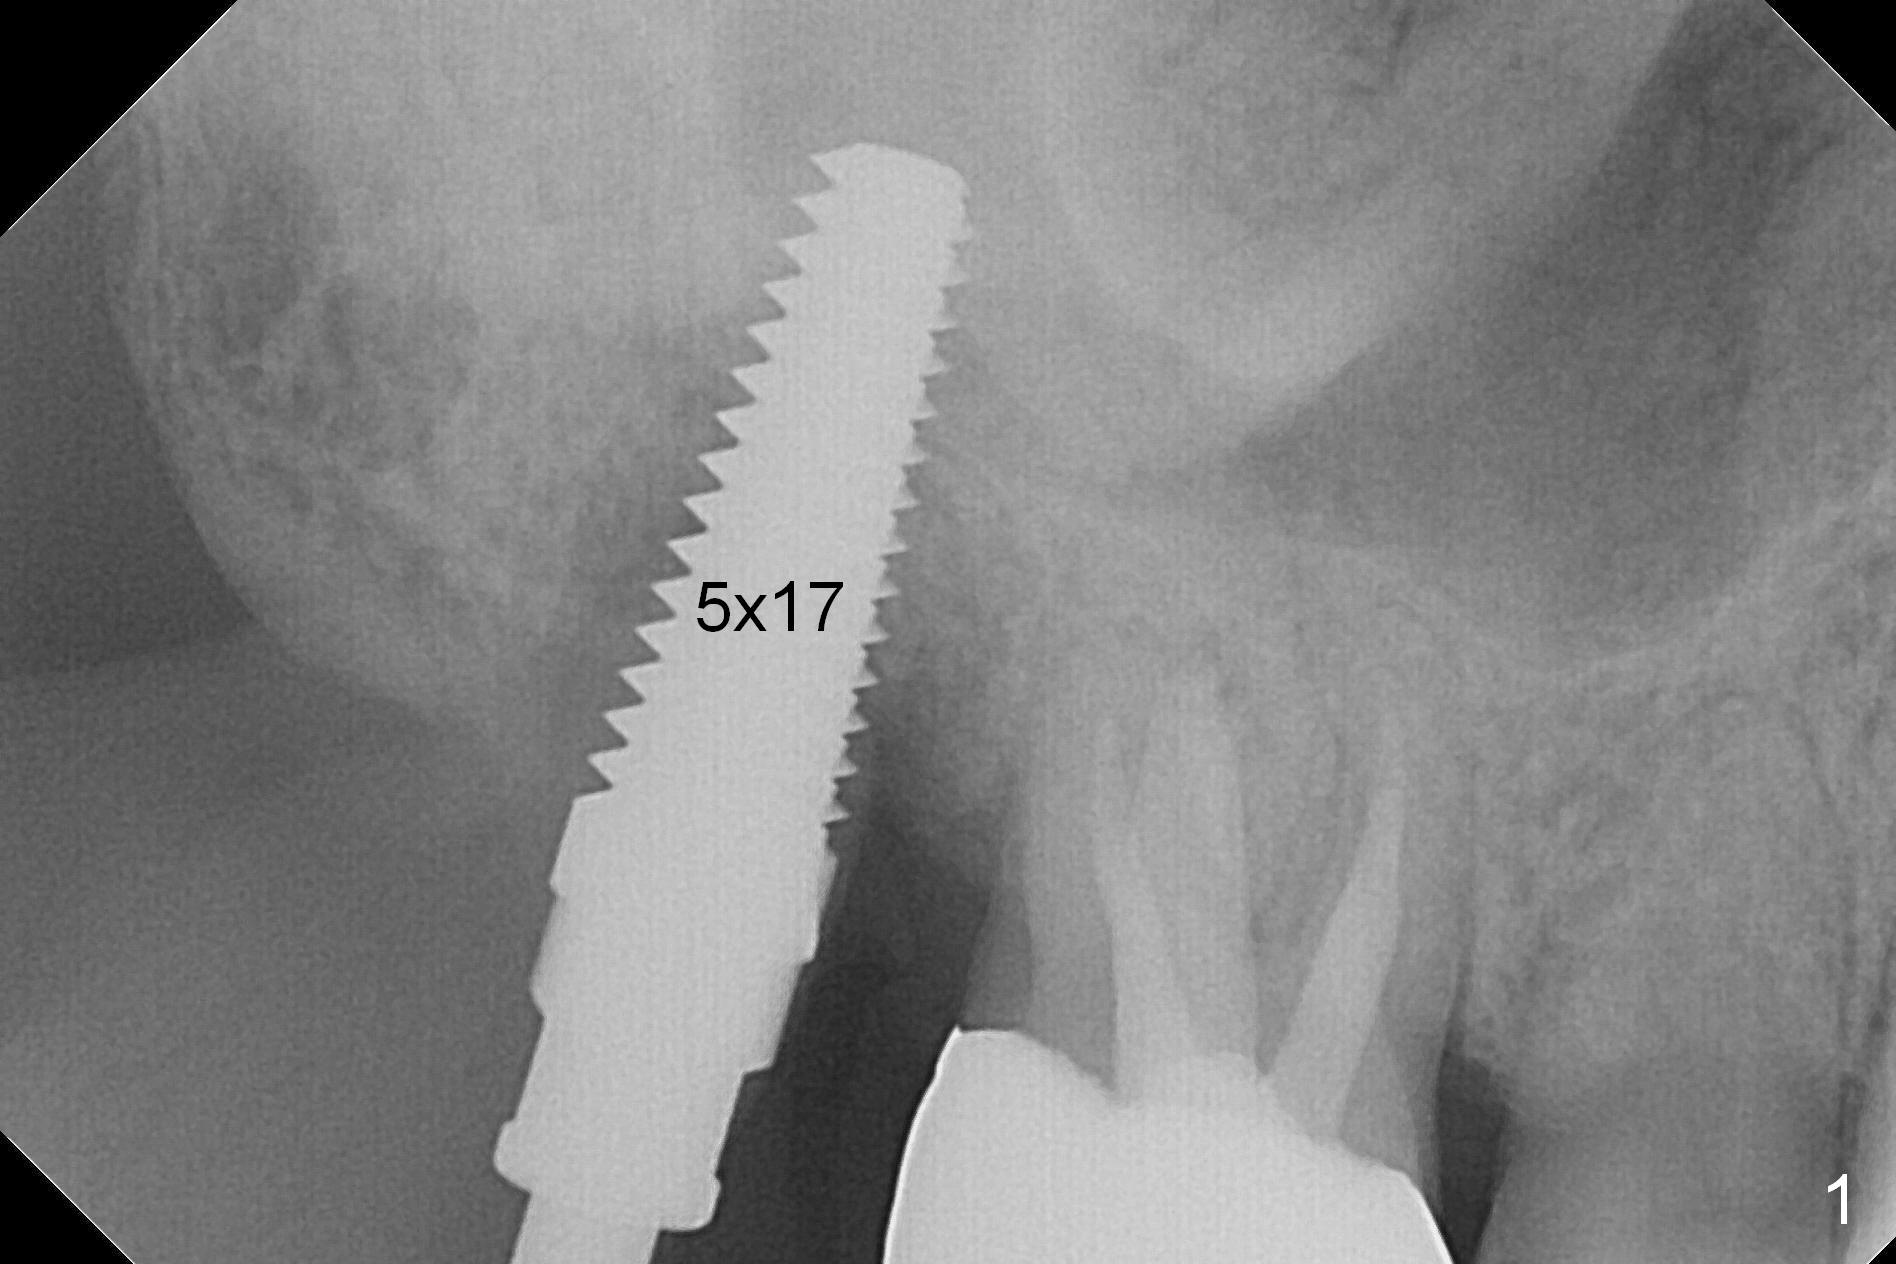

The tooth #2 is found to have fracture at extraction. The buccal (B) socket (*) has more resorption than the palatal (P) one (Fig. A (S: sinus). The buccal plate is also lower. Osteotomy is initiated in the buccal slope of the septum with Magic Expanders (ME, 3-4.8 mm, Fig. B (red)), followed by Tatum tapered tap drills (Fig. C (green), Fig.1 (5x17 mm)). As the diameter of ME and tap increases, the osteotomy is shifting buccally due to bone height discrepancy (Fig. C). A Lindamann bur is used to remove the palatal bone (Fig. D (pink) and move the osteotomy palatally (Fig. E). The coronal end of 7x14 mm tissue-level fixture (Fig.2) tilts buccally (Fig. F purple). Insertion torque is 35/40 Ncm. Prior to implantation, a piece of PRF membrane and allograft are pushed into the sinus. A 6x3 mm abutment (Fig.2) is immediately placed to keep an immediate provisional, bone graft and collagen membrane in place. Bone seems to have grown into the space between the implant threads 5.5 months postop (Fig.3). There is no bone loss 2 years 2 months post cementation (Fig.4).